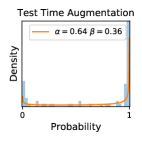

5.1 Distribution of Uncertainty Scores

Distribution of Uncertainty Scores Across Different Severity Levels As explained in Section 3, each uncertainty metric essentially defines an order/ranking among the data points. We conducted an analysis to better understand what data will be assigned high uncertainty under a particular uncertainty metric . Picking out the highest ranked data points (), we calculated the ratio of data points from each SL. Figure 4 summarizes the results as box plots for the Kaggle-DR and the Messidor-2 datasets; additional detailed statistics can be found in Table S.1 in the supplementary materials. From the plot and table, SL1 & SL2 examples account for a higher proportion among the top-ranked uncertain examples across the three ensemble methods. This finding matches our intuition that incipient disease examples (SL1 & SL2) are more likely to be considered uncertain by ensemble methods due to their ambiguity.

In contrast, the MC-dropout method showed the worst overall performance among the three, as it can be seen from the high ratios of SL0 examples among the uncertain negatives in Figure 4. The histograms in Figure 2 provides another perspective to look into the phenomenon, where a decent proportion of MC-dropout model’s predictions on SL0 inputs entailed low confidence (far from 0 or 1), which from another angle explained why MC-dropout was less specific in terms of lower FNP; many no-DR inputs (i.e. SL0) were erroneously assigned high uncertainty by MC-dropout models.

It is still an open question why the evaluated MC-dropout networks signaled relatively high uncertainty on SL0 & SL3 & SL4 data that are less likely to be ambiguous. We conjecture that much of the “uncertainty” indicated by disagreement among test-time dropout samples actually reflects the stochastic nature of dropout networks rather than the real decision uncertainty associated with the data. It is worth noting that the MC-dropout model we evaluated was not weak per se; they all achieved above Area Under Curve (AUC) scores on test sets. The weakness of individual test-time samples (which explains their low-confidence predictions on SL0 & SL3 & SL4) might have been hidden when they are aggregated into an ensemble—a well-known advantage of ensemble learning. Our results suggested that the uncertainty information given by implicit ensemble methods such as MC-dropout and TTA might not be as reliable as that from explicit ensemble approaches (e.g., stacking ensembles). Similar findings on MC-dropout can be found in some previous papers [1].